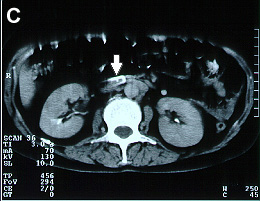

Imagens tomográficas da paciente após a trombose da veia cava inferior. Nota-se a sequência de A para E em que se vê a veia cava normal ao nível das veias renais e abaixo do clipe a veia cava trombosada (aumento do volume com forma circular e halo com captação de contraste)